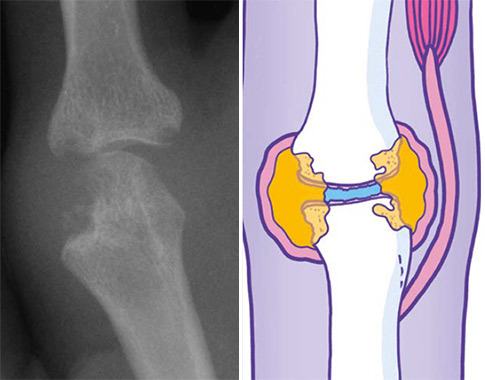

The structures that are shown below represent diagrammatically the changes that occur in the two main types of arthritis. However, it is important to identify those cases where pain may appear to arise from the joint but is in fact referred pain – for example, where the patient describes pain in the left shoulder, which might in fact be referred pain from the diaphragm, the neck, or perhaps ischaemic cardiac pain. In cases where examination reveals no abnormalities in the joint, other clues will be obtained by taking a thorough history. A common cause of widespread pain with normal joint examination for example is fibromyalgia.

X-ray and diagrammatic representation of an index finger MCP joint affected by rheumatoid arthritis